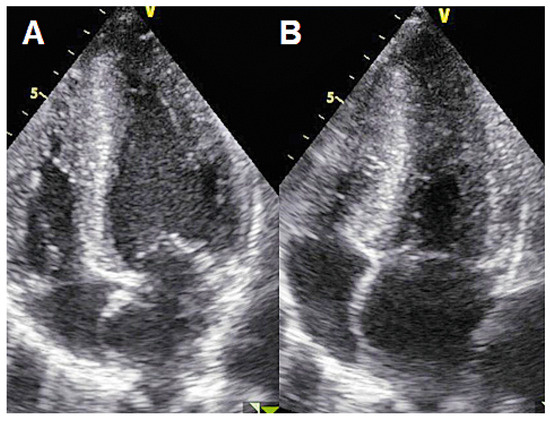

Atrial fibrillation is a cause of left atrial thrombus leading to cardioembolic stroke, which can be effectively prevented with oral anticoagulation. Right atrial appendage thrombus is a rare complication of atrial fibrillation that can also lead to cardioembolic pulmonary embolism. We present the case of a 71-year-old male with atrial fibrillation, thrombus in the right atrial appendage and pulmonary embolism. Full article

Show Figures

Figure 1